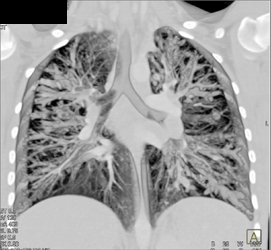

Cystic Fibrosis